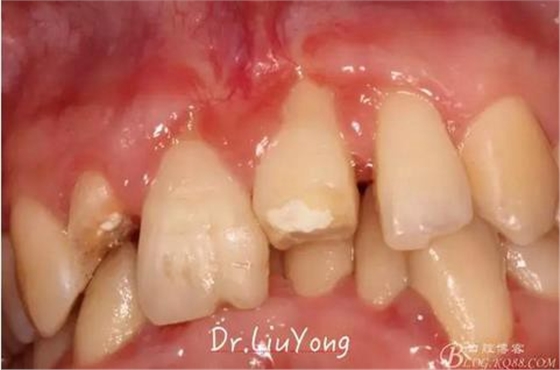

術(shù)后兩周復(fù)查,牙齦紅腫明顯好轉(zhuǎn),探診不出血,但是此時A1唇側(cè)牙齦角形退縮1.5mm,B1唇側(cè)牙齦退縮3.5mm,B1遠(yuǎn)中牙齦乳頭萎縮明顯,B2近中牙齦萎縮約1mm,且A1B1B2牙齦退縮處角化牙齦幾乎缺失,同時上唇系帶直接牽拉于B1齦緣?;颊邽楦咝€女性,露齦笑,由于存在前牙區(qū)牙齦的高度嚴(yán)重不對稱及前牙牙冠過長的問題,因此嘗試通過膜齦手術(shù)改善患牙牙齦退縮。通過術(shù)前分析,A1唇側(cè)牙齦退縮屬于Miller分類第一類, B1唇側(cè)牙齦退縮屬于Miller分類第3類(B1遠(yuǎn)中牙齦乳頭為2類,Nordland and Tarnow分類法),B2唇側(cè)牙齦退縮屬于Miller分類第3類,由于擬采用冠向復(fù)位瓣的方式治療牙齦退縮,因此需要先行上唇系帶修整術(shù),解除上唇系帶帶來的過大牽引力。

潔治刮治后2周,如上圖